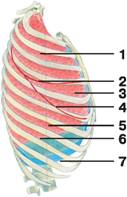

Рис. Границы легких

Рис. Границы легких

А — вид спереди:

1 — верхняя доля легкого;

2 — передняя граница плевры

3 — передний край легкого: а) правого; б) левого;

4 — горизонтальная щель;

5 — средняя доля;

6 — нижний край легкого: а) правого; б) левого;

7 — косая щель;

8 — нижняя доля;

9 — нижняя граница плевры;

Рис. Границы правого легкого (вид сбоку):

1 — верхняя доля;

2 — горизонтальная щель;

3 — средняя доля;

4 — косая щель;

5 — нижняя доля;

6 — нижний край легкого;

7 — нижняя граница плевры